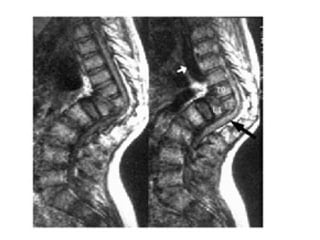

Tuberculosis of the

Spine- Pott’s Disease

• As a form of extrapulmonary tuberculosis that impacts the

spine, Pott’s disease has an effect that is sometimes

described as being a sort of arthritis for the vertebrae that

make up the spinal column. More properly known as

tuberculosis spondylitis, Pott’s disease is named after Dr.

Percivall Pott, an eighteenth century surgeon who was

considered an authority in issues related to the back and

spine.Pott's disease is often experienced as a local

phenomenon that begins in the thoracic section of the

spinal column. Early signs of the presence of Pott’s

disease generally begin with back pain that may seem to

be due to simple muscle strain. However, in short order,

the symptoms will begin to multiply.